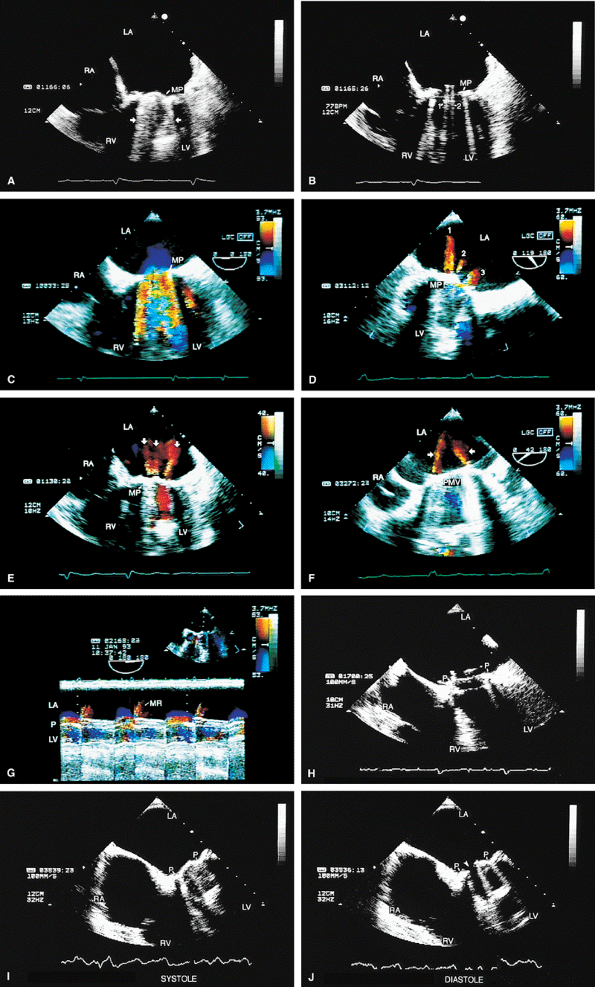

FIGURE 5.1. St. Jude mitral prosthesis: normal. The mitral prosthesis (MP) is seen in the closed (A) and open (B) positions. A. Prosthetic reverberations or artifacts (arrows) that clutter the left ventricle (LV). B. The two leaflets (1 and 2) of the prosthesis in the open position together with the reverberations. C. Aliased diastolic inflow into the LV is seen with a small region of flow acceleration. D–G. Two to three small jets of mitral regurgitation (MR; arrows) are shown. These are normal findings. Usually, these jets are narrow and do not show significant turbulence but may extend deep into the left atrium (LA). G. illustrates the norm (not pansystolic). H. Small linear echoes are normally seen on both the atrial and ventricular aspects of the prosthesis and represent suture material. I, J. Immediately postsurgery, although the patient is still on partial bypass, one leaflet of the prosthesis (P) may intermittently fail to open. This should not be mistaken for dysfunction. When cardiac output improves, normal opening of both leaflets occurs consistently. RV, right ventricle; RA, right atrium. |